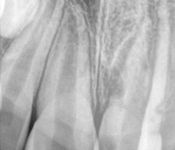

Pictured: Preoperative, Retreatment, Apicoectomy

and 5 Year Recall

Our patient required root canal retreatment. After an apicoectomy, the removal of the root tip and the infected tissue, there was complete bone healing in the 5 year recall.